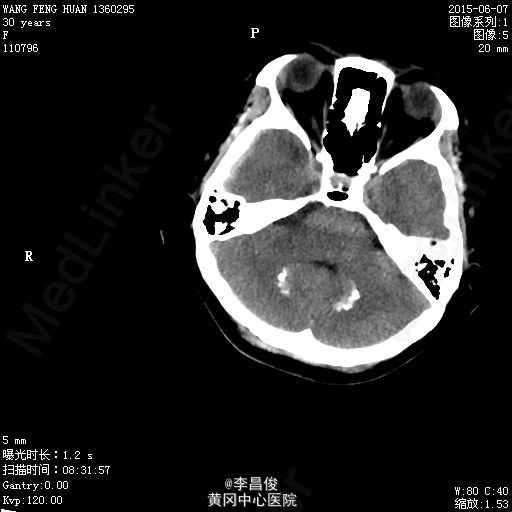

入院完善相关检查:血常规:血红蛋白 105.1g/L,血小板 95*10^9/L,尿常规:蛋白 -,肝功能:谷丙转氨酶 77.9U/L,尿酸 426.7umol/L,凝血机制:D-二聚体 2267ng/ml。 血脂:甘油三酯:3.31;低密度脂蛋白:5.46,甲功、心肌三项、心脏彩超正常, 给予对症处理,患者于6月4 日8:42分在会阴左侧切下以LOA位顺利娩出一活女婴,产程顺利,产时血压最高达160/110mmHg,给予心痛定一粒舌下含服,产后回病房后监测血压在100-140/70-90mmHg之间波动。6月7日5点多头痛明显,急查头部CT提示:右侧额颞顶部硬模下血肿。请神经外科急会诊,建议转专科治疗。转外科后,患者意识障碍加重,6月8日17:30时急诊全麻下行“右侧开颅硬膜下血肿清除+去骨瓣减压术”,术后转重症医学科。稳定后拔除气管插管后转回专科,行抗感染、止血、神经营养、脱水治疗,定期换药及CT复查,后出现癫痫发作,给予抗癫痫治疗。6月13日患者癫痫发作后呈持续状态,药物控制不理想,故转入ICU进一步监护治疗。患者神志昏迷,给予持续泵入丙戊酸钠、咪达唑仑控制抽搐,适当脱水、抗感染、营养支持及对症处理,并及时复查相关检查。患者癫痫控制后于17/6日顺利拔除气管导管。于17/6日再次癫痫发作1次,很快缓解。转神经科继续治疗:患者神志清楚,精神、食欲一般,诉左侧肢体无力伴麻木,无抽搐发作,右侧肢体肌力尚可,左侧肢体肌力3级。肌张力不高。继续给予抗癫痫、适当抗感染、肢体康复训练及对症支持治疗,一周后行颅脑MRI:未见明显异常;查体:心肺听诊(-),腹软,压痛反跳痛,双下肢无水肿,右侧肢体肌力尚可,左侧肢体肌力5级-,病理征(-),给予办理出院。